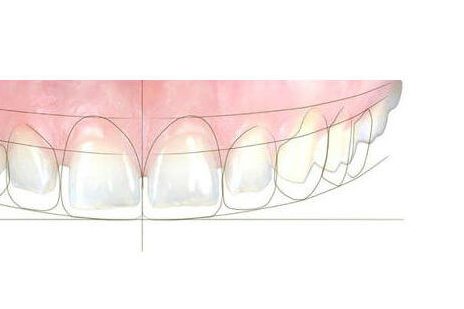

Dentisterie esthétique

La dentisterie esthétique vise à améliorer l'apparence du sourire en intervenant sur la couleur, la forme et l'alignement des dents. Elle est donc multidisciplinaire et peut faire intervenir d'autres spécialités comme l'orthodontie et la chirurgie.